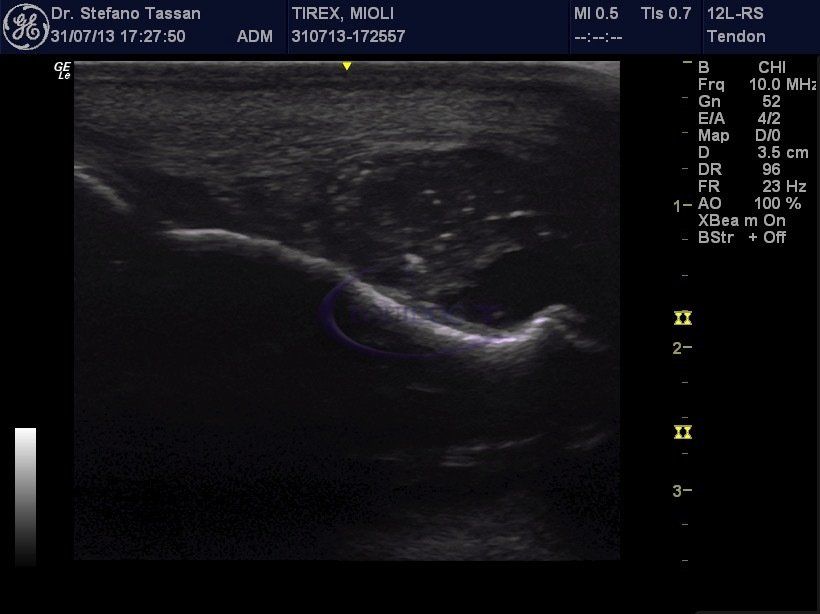

Diagnostica

La Radiologia Diretta (DR) rappresenta la più moderna tecnica radiografica digitale in alta definizione. Scopri tutti i Servizi →